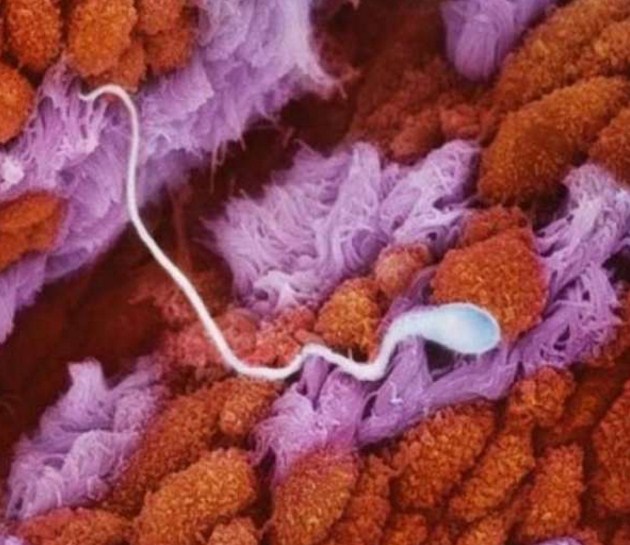

Яйцеклетката.

Един от 200-та милиона сперматозоида на бащата прониква през клетъчната мембрана на яйцето.